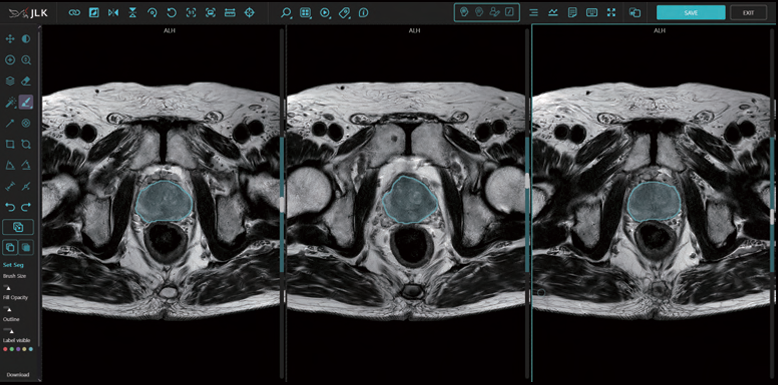

제이엘케이는 이번 결정으로 전립선 MR 영상을 복합적으로 분석하고, AI가 PIRADS 진단 및 PSA(전립선 특이 항원, Prostate-Specific Antigen) density 진단 등 전립선암 진단에 필요한 모든 데이터를 제공하는 ‘MEDIHUB Prostate’의 기술적 우수성을 다시 한번 증명하게 됐다.

제이엘케이의 ‘MEDIHUB Prostate’는 이미 지난달 미국 FDA 승인을 받는 등 국내뿐 아니라 글로벌 기술 검증을 마쳤다. 특히, 국내 서울아산병원과 해외 미국 미주리 대학과의 임상시험으로 다양한 인종적 특성을 모두 감안해 개발됐다는 평가를 받고 있다.